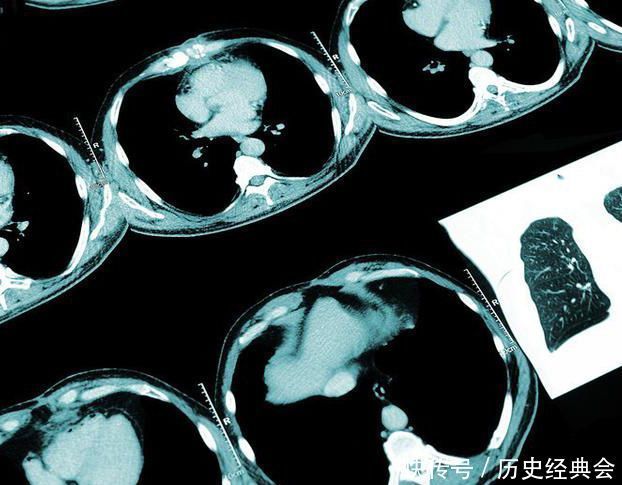

肺气肿在X线表现为胸廓扩张,肋间隙增宽,肋骨平行,膈降低且变平,两肺野透亮度增加。胸部CT可表现为大片状无壁低密度区;或局限性肺透亮度增高,其中可见点状高密度影,即肺血管。周围血管变细、稀疏;而肺门血管增粗、增大。肺癌在CT上表现为肿块影,可以是实性的,部分实性,也可以是磨玻璃结节,其密度都是高于空气的,在CT的肺窗表现为发白的不规则影,而纵膈窗可见明显肿块影,或者合并阻塞性肺炎、肺不张。